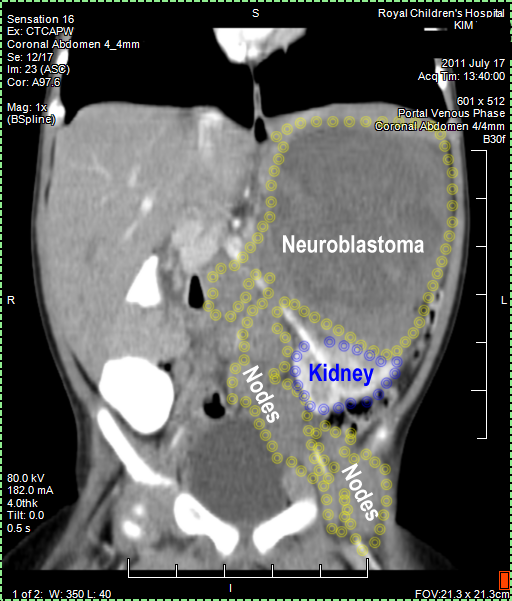

Kim's Neuroblastoma IV,

N-Myc amplification

CT (CAT) scan 17July 2011